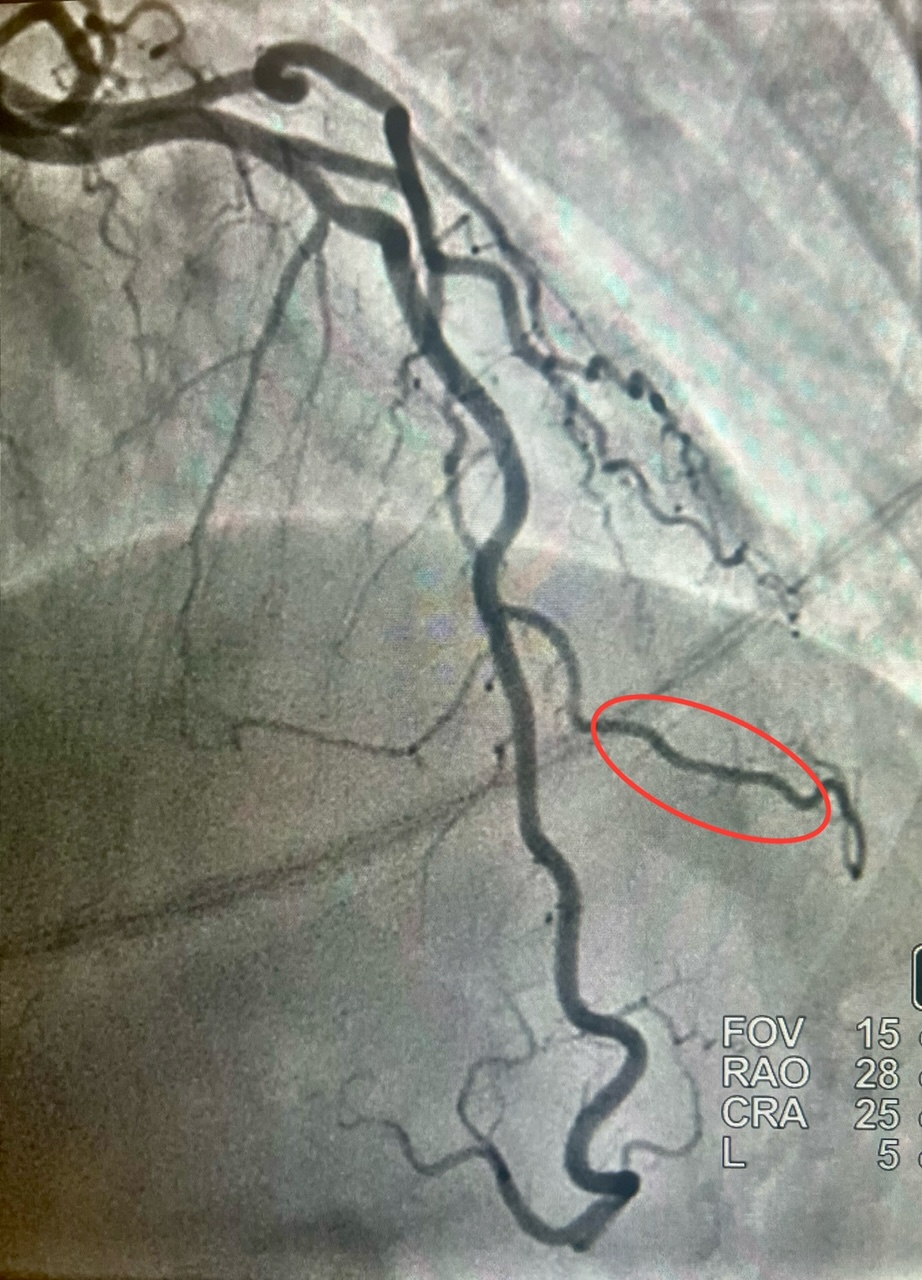

We present a 54-year-old woman with a medical history of opioid addiction, anxiety disorder, and current cigarette smoker who presented to the hospital via Emergency Medical Service after an episode of syncope at home. (Figures 1 and 2). The patient continued to have recurrent episodes of ventricular tachycardia along with elevated troponins, with an echocardiogram that showed reduced LV ejection fraction with slightly more pronounced hypokinesis of the septal and apical walls; thus, the decision was made to rule out ischemia as a possible cause. She subsequently underwent coronary angiography via the right radial approach, which revealed a right-dominant system, and normal coronary arteries, with the exception of the second diagonal branch of the LAD, which had severe systolic compression, resulting in obliteration of the artery with each cardiac cycle. Angiographically, when a vessel completely obliterates during cardiac catheterization, it is referred to as a “milking” phenomenon (Video).